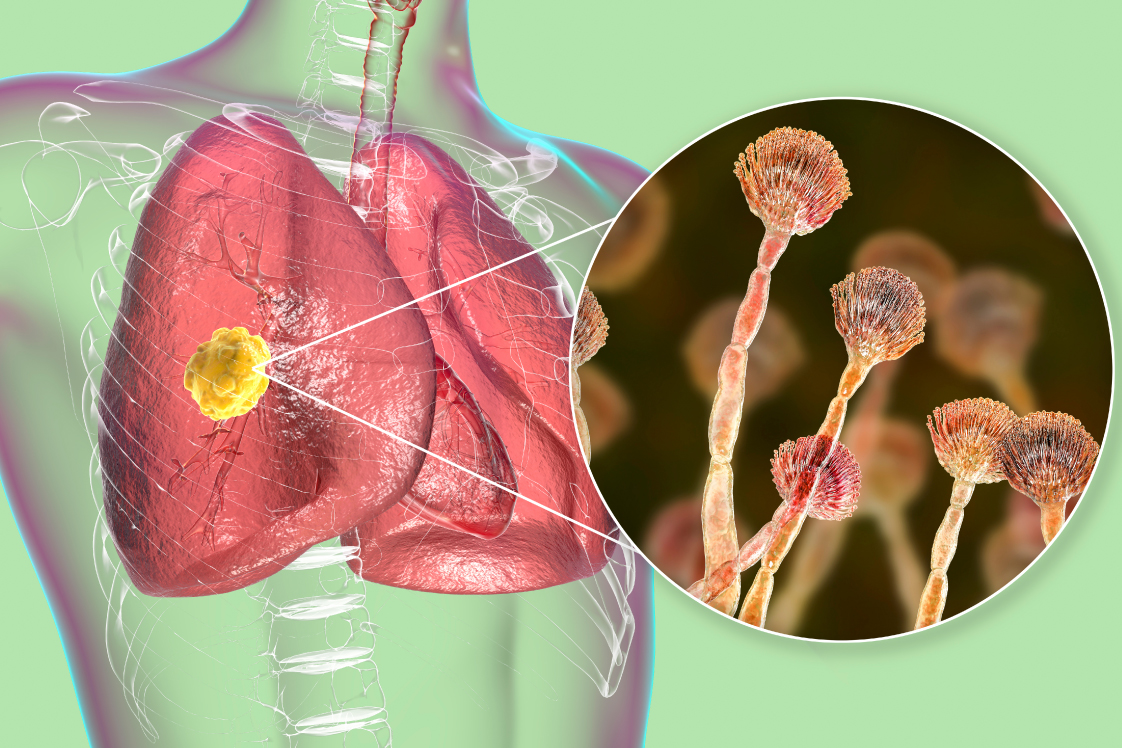

肺アスペルギルス症

アスペルギルス(真菌の種類)による肺真菌症は、侵襲性、慢性、単純性、アレルギー性の4つのタイプに大別されます。これらは、それぞれ異なる基礎疾患、経過、治療法を持っており、正確な診断と適切な治療が重要です。